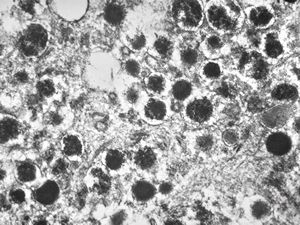

F,68y. | APUD carcinoma

F,68y. | APUD carcinoma (Bodian siver impregnation)